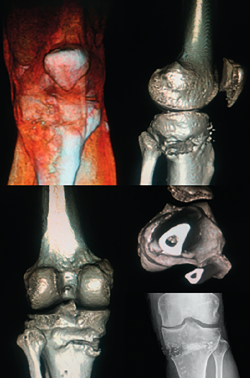

Meniscal root lesions

Meniscal root lesions are lesions located at less than 1 cm from the bone insertion of the meniscus, or lesions that involve bone avulsion of the anchoring zone (Figure 4). While lesions of the posterior root of the medial meniscus are related to degenerative processes, lesions of the posterior root of the external meniscus are associated to lesions of the ACL (7-12%)(30). Rupture of the posterior root of the medial meniscus biomechanically behaves like a total meniscectomy(31), while rupture of the posterior root of the external meniscus associated to ACL rupture results in an increase in anterior translation of the tibia and adds increased rotational instability, incrementing pivot shift(32).

[[{"fid":"4713","view_mode":"default","fields":{"format":"default","alignment":""},"type":"media","field_deltas":{"4":{"format":"default","alignment":""}},"link_text":null,"attributes":{"class":"media-element file-default","data-delta":"4"}}]]

Diagnosis

From the clinical perspective, these lesions should be suspected in the presence of Lachman scores of 3+ and pivot shift. High field MRI has been shown to be the diagnostic imaging test with the greatest sensitivity and specificity(33). Three radiological signs are associated to damage to the posterior root: 1) a hyperintense signal perpendicular to the meniscal root in the axial plane; 2) a vertical lineal defect over the meniscal root (truncation sign), which is associated to a meniscal extrusion of over 3 mm; and 3) the "ghost sign", representing the absence of meniscus in the sagittal plane in the zone of the posterior root(34,35).